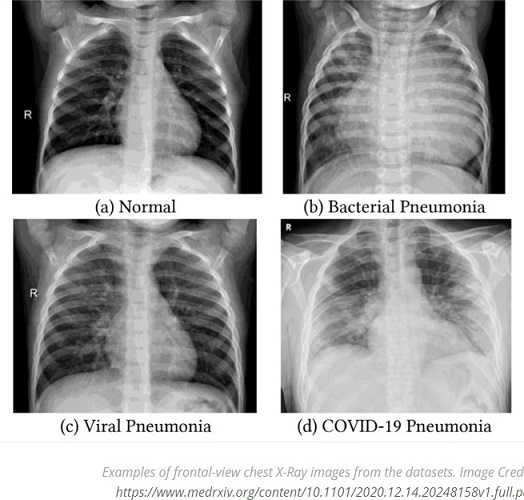

White Lung Syndrome

มีการนำภาพเอกซเรย์ปอดสีขาวโพลนมาเชื่อมโยงกับการป่วยด้วยโรคปอดอักเสบในรัฐโอไฮโอ โดยอ้างว่าเป็นกลุ่มอาการ White Lung Syndrome หรือสภาวะที่ปอดเกิดการอักเสบจนภาพเอกซเรย์ปอดกลายเป็นสีขาว เนื่องจากเกิดการอักเสบอย่างรุนแรงหรือมีของเหลวอยู่ภายในปอด

อย่างไรก็ดี White Lung Syndrome ไม่ใช่ศัพท์ทางการแพทย์ ส่วนภาพเอกซเรย์ปอดมักจะพบในกลุ่มผู้ป่วยที่มีอาการหายใจลำบากเฉียบพลัน (ARDS) แต่ไม่พบว่าเด็กที่ป่วยเป็นโรคปอดอักเสบมีอาการรุนแรง จนภาพเอกซเรย์ปอดเป็นสีขาวโพลนหรือ White Out ตามที่กล่าวอ้าง